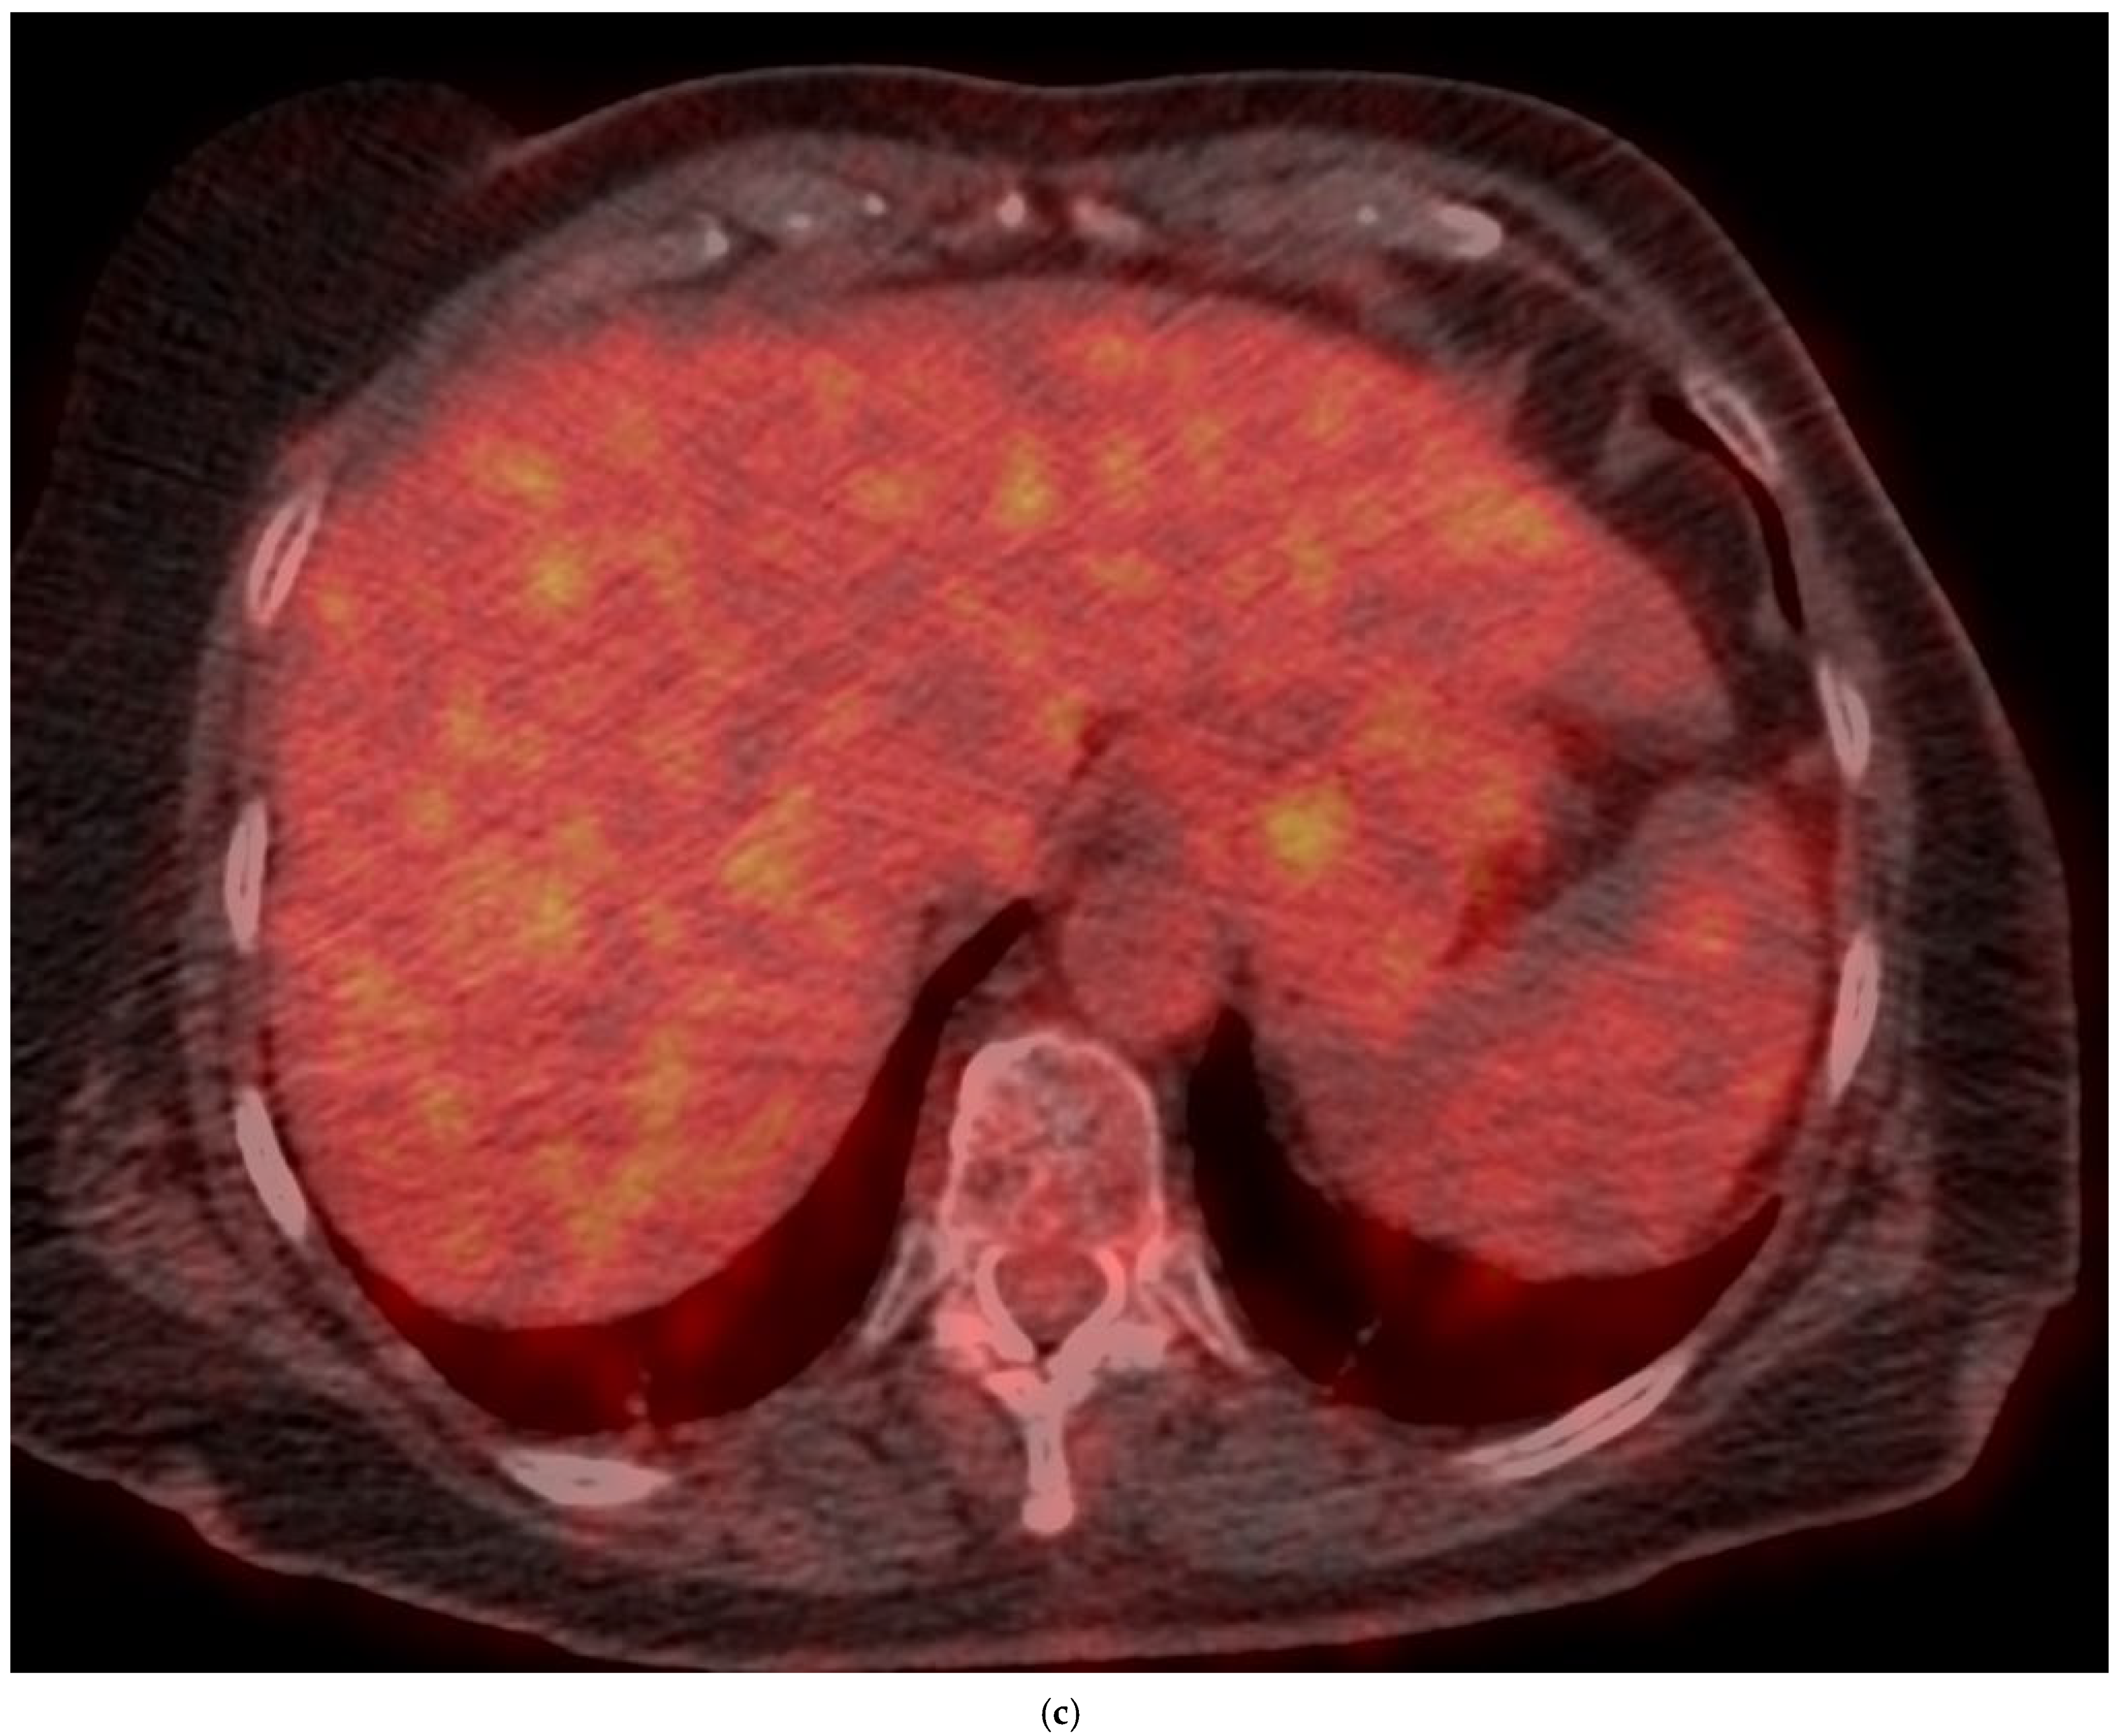

4. Clinical Characteristics of VIAs-Patients